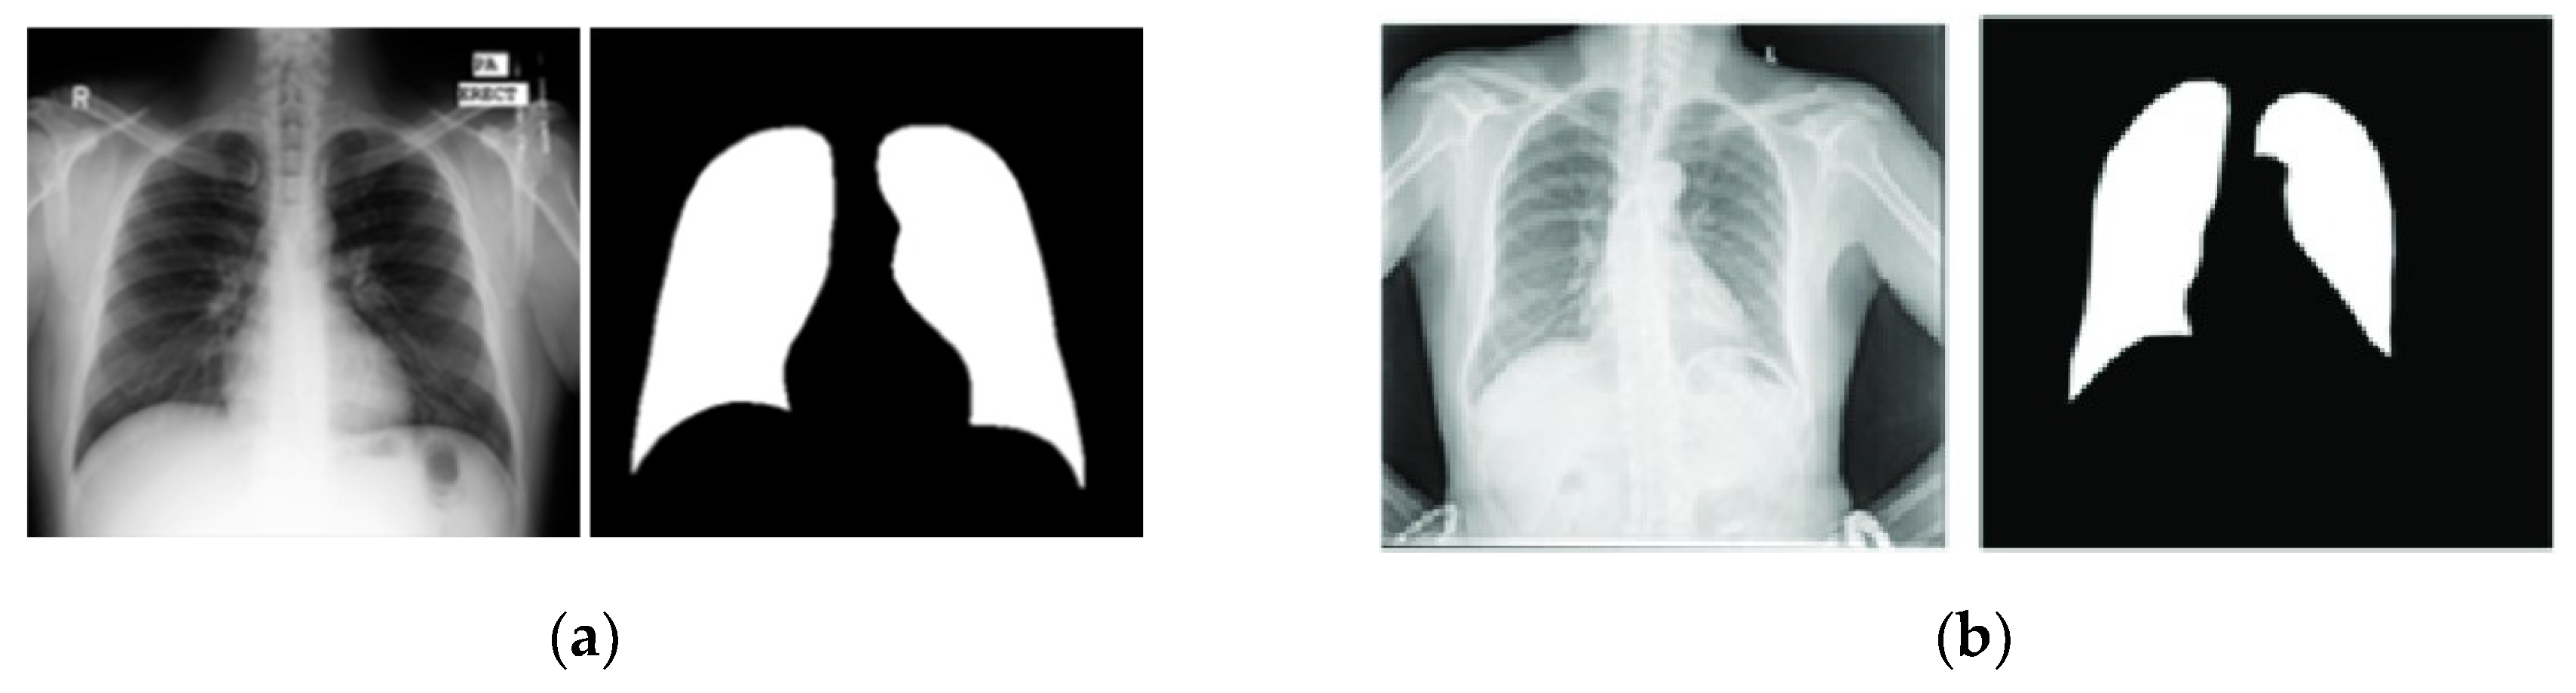

2.2.3. Shenzhen Hospital & Montgomery County Chest X-ray Sets

The Shenzhen and Montgomery CXR sets consist of images obtained from their respective regions in China and the United States and are publicly accessible. While these datasets are primarily used for classification tasks, their application has been extended to include lung segmentation tasks [24,25].

The Shenzhen dataset contains 662 CXR images with a resolution of approximately 3000x3000 pixels. Unlike the previously mentioned datasets, the Shenzhen dataset does not include corresponding ground truth masks. Instead, segmented masks created by students and teachers from the Department of Computer Engineering at the National Technical University of Ukraine were utilized as ground truth masks [24,25,26]. However, since 96 out of the 662 images lack segmentation masks, this study used only the remaining 566 images with available masks. On the other hand, Montgomery’s dataset included 138 CXR images with their ground truth masks. Image size varied from 1255x989 to 3001x3001 pixels. In this paper, we adopted the widely used methodology from the literature, in which the first dataset was utilized for training, and the second dataset was employed for testing the models [24,25,26]. Figure 7 presents representative examples of each dataset.

Figure 7. Images from (a) Shenzhen Hospital CXR Set; (b) Montgomery County CXR Set.